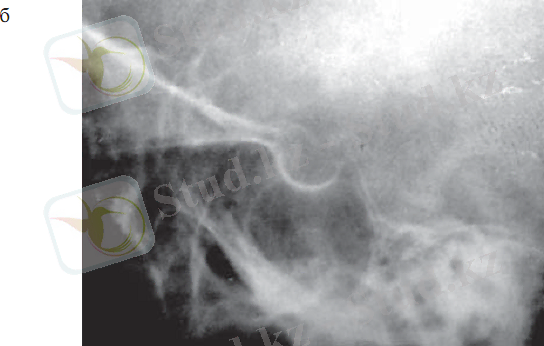

Гипофиздің интраселлярлы ісіктерінің рентгендиагностикасы түрік ершігінің өлшемдерін анықтауға негізделеді. Қалыпты жағдайда түрік ершігінің өлшемдері тең: сагиттальды - 12-15 мм, вертикальды- 8-9 мм (2. 2 сурет) .

2. 2 сурет. Рентгенкраниография:

а - түрік ершігінің рентгенографиялық бағдарлары;

б - қалыпты жағдайдағы түрік ершігінің рентгенограммасы

Гипофиздің үлкен аденомалары түрік ершігі өлшемдерінің үлғаюына, кіреберісінің кеңеюіне, сына тәрізді сүйек өсінділерінің жіңішкеріп, қысқаруына, түбінің тереңдеуіне, ершік арқасының бұзылуына, екі контурлы болуына (бір немесе екі кескіннің нақты болмауы) әкеледі, дегенмен бұл ешқандай диагностикалық қиындықтар тудырмайды (2. 3 сурет) . Түрік ершігінің шекарасынан аспайтын гипофиз микроаденомаларының рентгенограммаларында ешқандай өзгерістер анықталмайды.